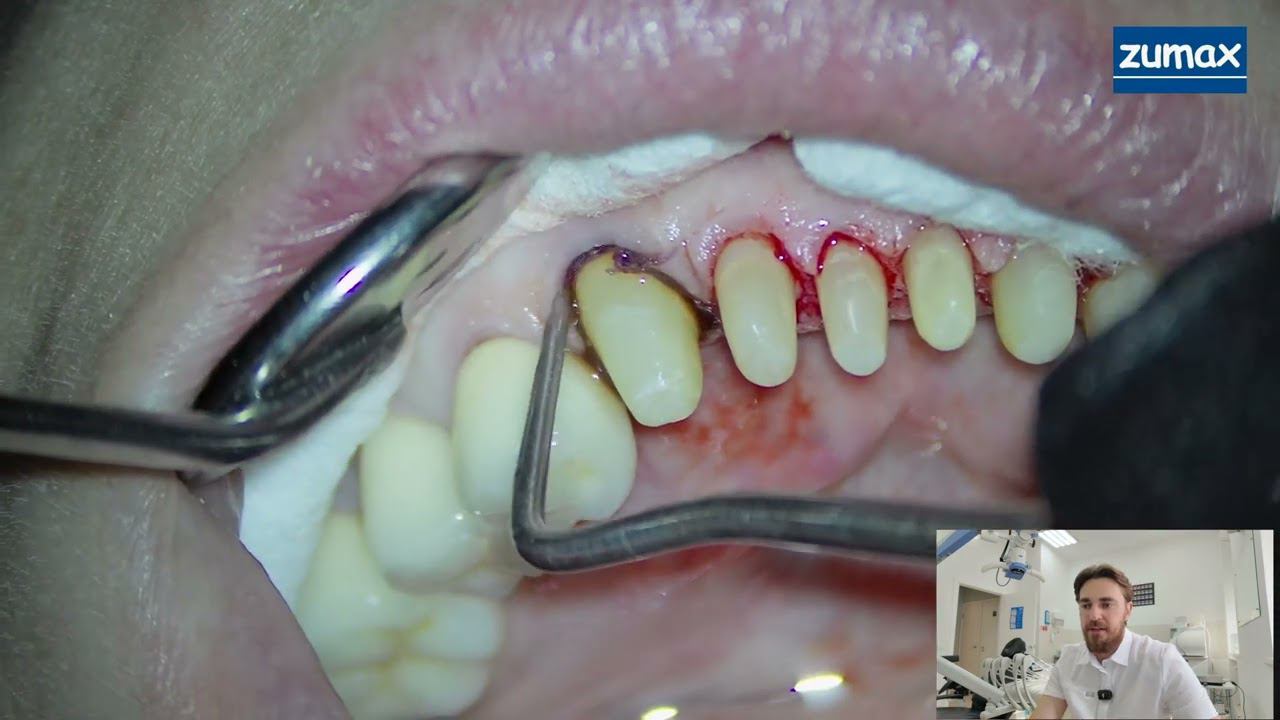

СТОМБУДНИ#40 САМЫЙ БЫСТРЫЙ ВЕРТИПРЕП С "КЕТЧУПОМ" И ОТТИСК смотреть онлайн 16:20

СТОМБУДНИ#40 САМЫЙ БЫСТРЫЙ ВЕРТИПРЕП С "КЕТЧУПОМ" И ОТТИСК